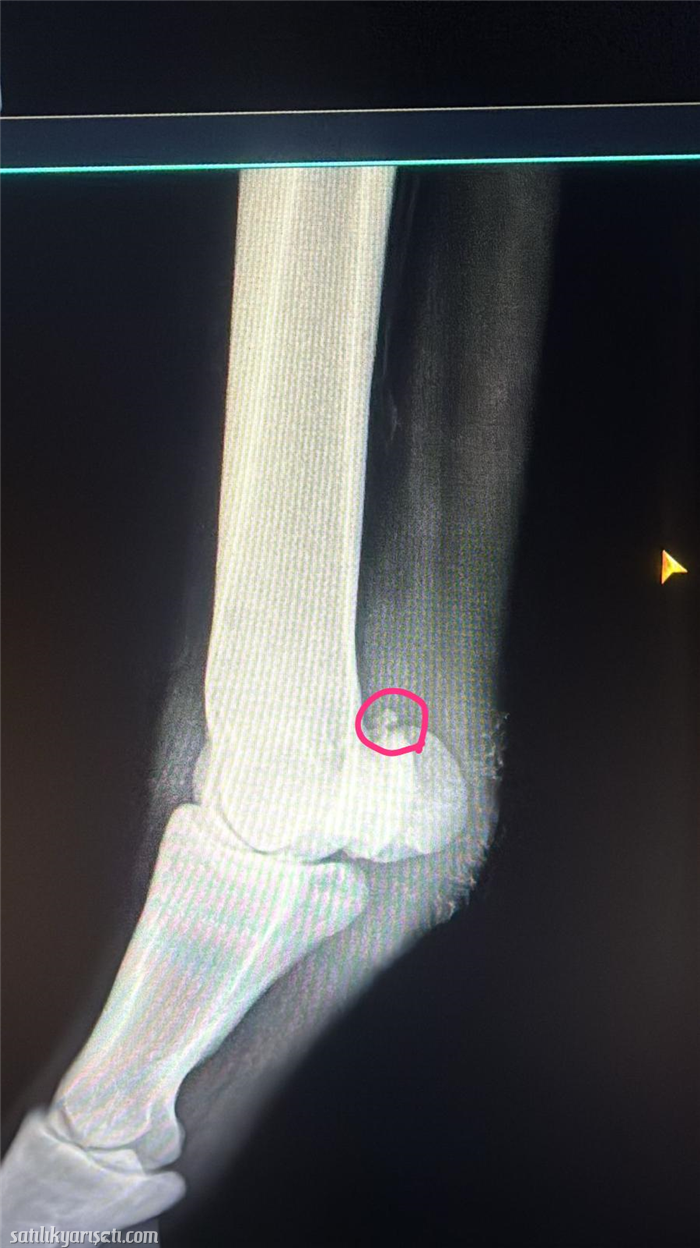

TAY KARACABEYDE DOĞDU BUYUDU BURSA HIPODROMDA 5 AYDIR HEM GUCLENDIRMESI HEMDE BOL BINEKLERI YAPILIP TIRISA GIRMISTIR . ATIN ARKA SAĞ SUSAMKEMIGININ USTUNDE RONTGENI KOYDUM UFAK BIR PARCA VAR O PARCA DAN DOLAYI GUCLENDIRMELER YAPTIM EN SON KOK HUCRE YAPTIM 2 KUR VE PRP LERDE NALINI SIMIT NAL TAKIP ORAYI DESTEKLEDIK DAHA KUVETLENSIN DIYE ATTA SORUN YOK HERHANGI BIR TOPALLAMA FILAN OLMADI HIC BIZ SADECE ONLEM ALARAK ARKA AYAKLARINI HEP BANDAJ VE IDMANDAN SONRA BUZ YAPIYORUZ YANI ILGI ISTIYEN BIR DURUM ARTIK BEN YURT DISINDA OLDUĞUM ICIN UZAKTAN OLMUYIR ONDAN BOYLE UYGUN FIYATI YAZDIM SADECE HIPOROOMDA HARCADIĞIM PARA ISTEDİĞMDEN DAHA FAZLA KARACABEY BAKIM AYGIR PARASI SAYMIYORUM.